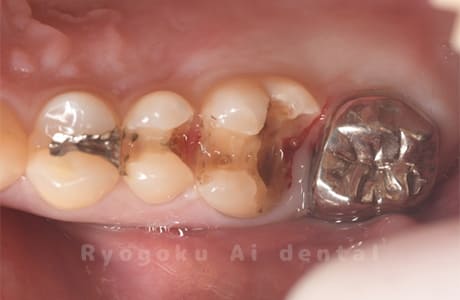

Case11

-

- 原因

- インレー2次カリエス、ならびにインレー脱離

- 治療内容

- セラミッククラウン、セラミックインレー

- 治療費用

- 123,000円×2(セラミッククラン)、77,000円(セラミックインレー)

銀歯が取れて、ご来院された患者様です。奥歯2本をセラミッククラウン、手前の小臼歯をセラミックインレーで治療を行いました。

<リスク・副作用>

過度の咬合や衝撃で割れることがあります。